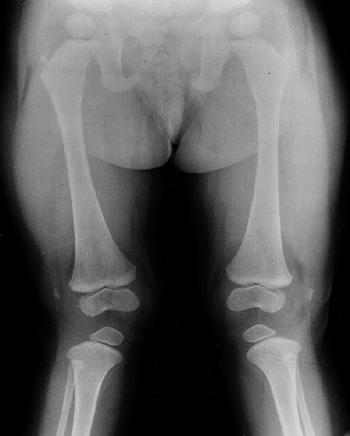

metaphyses of all long bones are flared in appearance. The diaphyses of

tibial metaphyses contributes to abnormal knee alignment (Fig. 8.7).

Figure 8.7

Radiograph of the lower extremities in a six-year-old with achondroplasia. The distal femoral physes have a pronounced inverted-“V” shape, and the knee is in varus. The acetabular roofs are horizontal. |